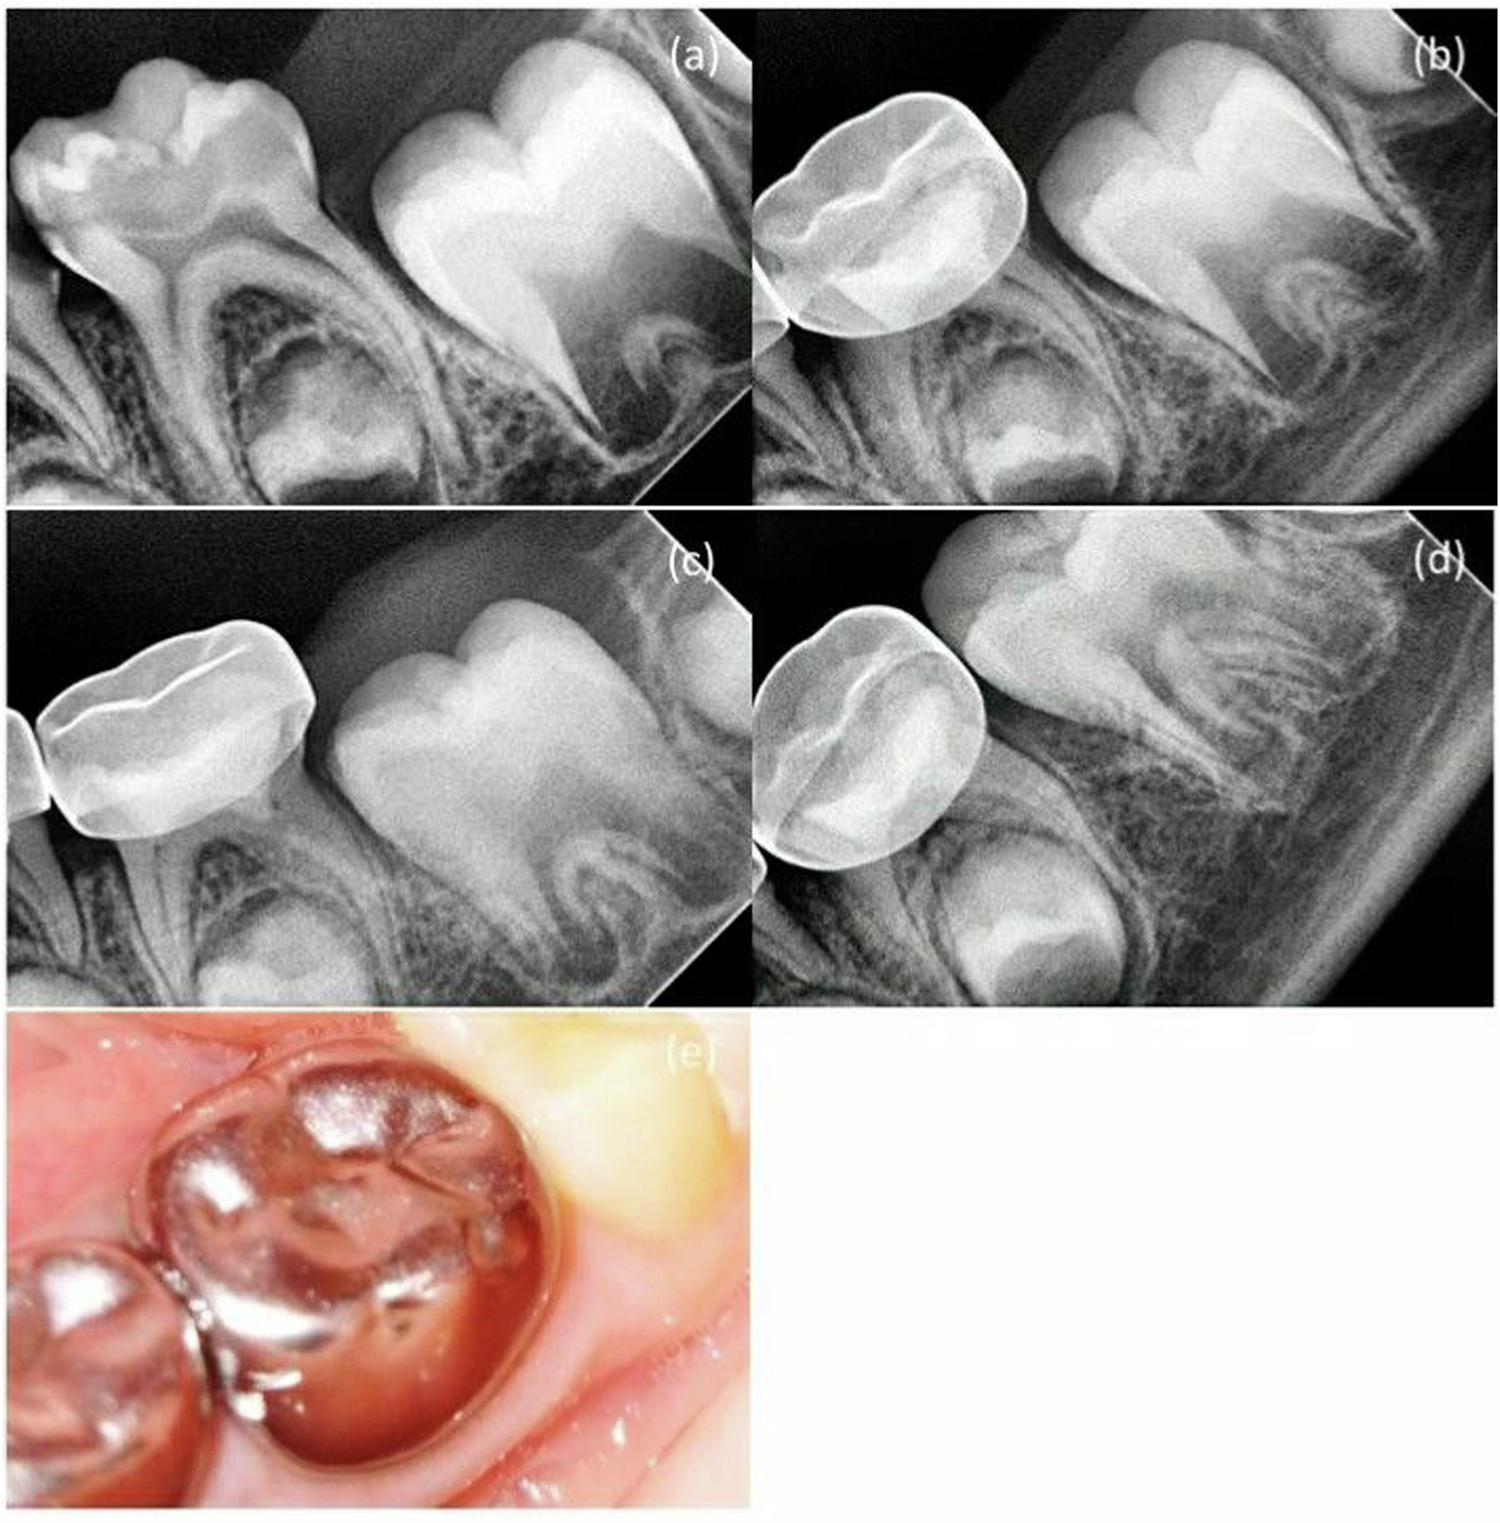

Fig. 3: MTA + NaOCl gel group in second primary molar pulpotomy in a female participant aged 5 years.

a A preoperative radiograph. b 3-month follow-up. c 6-month follow-up. d 12-month follow-up. e A photograph after 12-month follow-up.